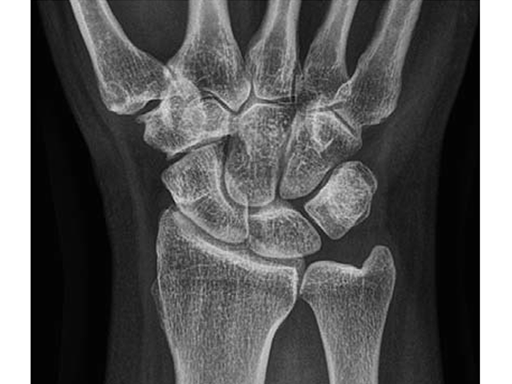

A 69-year-old female patient had suffered a right distal radius fracture one year earlier, and received conservative management. Symptoms included pain and impaired function about the wrist and forearm, with decreased forearm rotation. Painful DRUJ (DASH: 34, PWRE: 29).

The amount of correction required was 2.5 mm. The preoperative x-ray showed positive ulna variance.